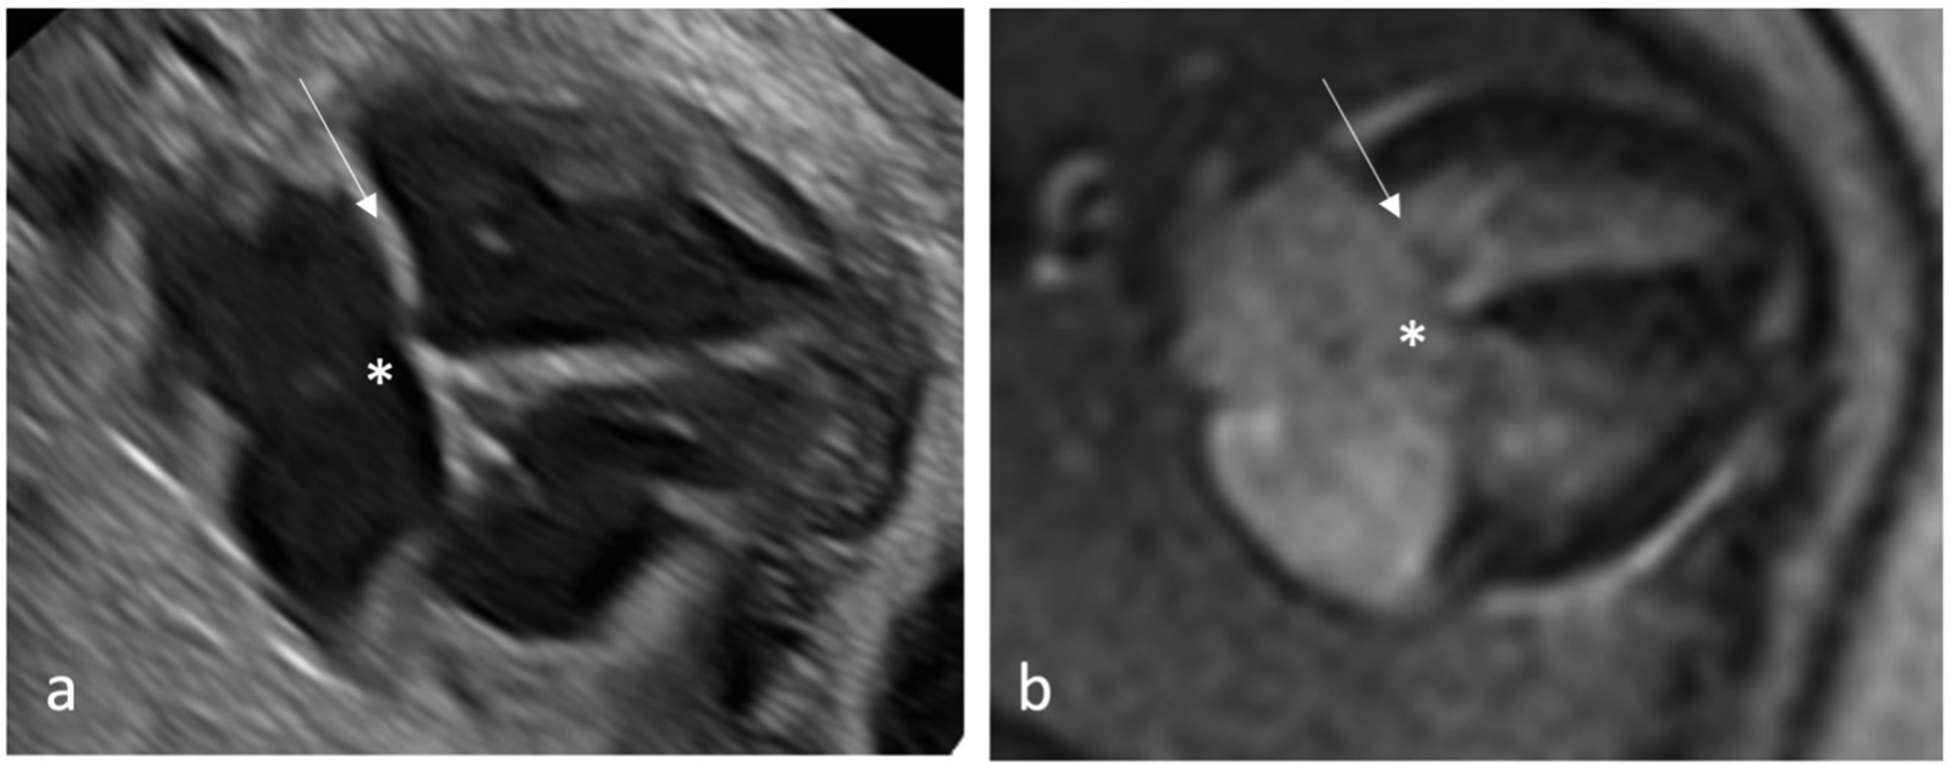

Figure 2

Qualitative assessment of fetal cardiac 4CV on fetal echocardiography (a) and DUS gated fetal cardiac MRI (b) with intermediate type AVSD detected by both methods. An AVSD, as shown here, is an atrial septal primum defect and an inlet ventricular septal defect (asterisk) with a combination of an abnormal common atrioventricular valve with a linear insertion (arrow).